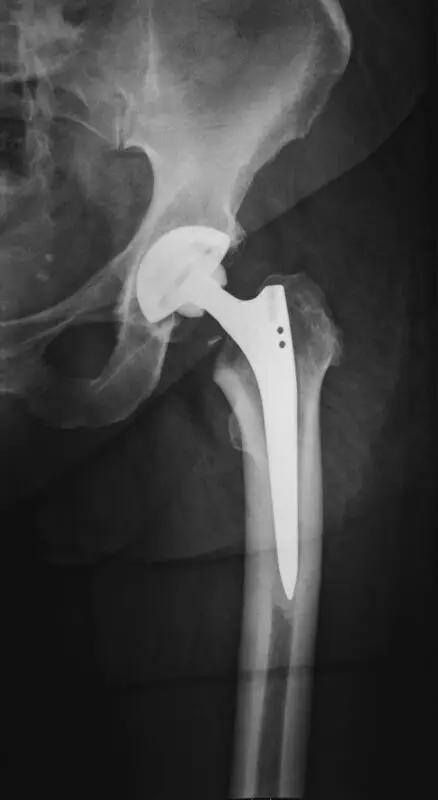

Total Hip Arthroplasty (THA), also known as hip replacement surgery, is a procedure where a damaged or arthritic hip joint is replaced with a prosthetic implant. It is designed to relieve pain, improve function, and restore mobility to individuals with severe hip joint issues.